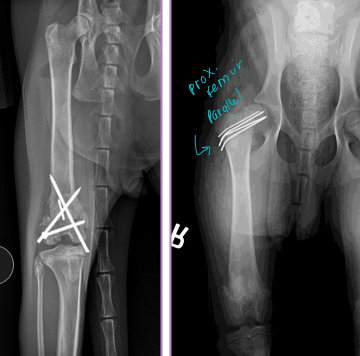

Femur Fractures

Capital Physis: Salter-Harris I, skeletally immature

Dt: AP & frog-leg radiographs

Tx: K-wires (diverging/parallel), temp“apple-coring” due to pins and blood supply

Diaphyseal fractures (#1)

Tx: plate + screws, interlocking nail, IM pin + cerclage

ESF not recommended as no safe corridors

Distal Physeal fractures: young, Salter-Harris type, growth plate involvement

Tx: cross pins (linear), plates (if comminuted)

Risk of quadriceps contracture(esp. extended postion) peg leg